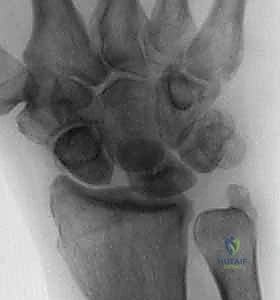

- التصوير بالأشعة السينية (X-rays): يتم أخذ صور شعاعية في وضعيات متعددة (أمامية خلفية، جانبية، وبقبضة مغلقة Clenched Fist View). وضعية القبضة المغلقة تزيد الضغط على المفصل وتُظهر بوضوح الفجوة بين العظمين (علامة تيري توماس) إذا كان الرباط ممزقاً.

يُسبب تشوه DISI، الذي يتميز بتمدد العظم الهلالي غير المرتبط وانثناء الزورقي، اتساعًا واضحاً في المسافة الزورقية الهلالية (تُعرف إشعاعياً بعلامة تيري توماس "Terry Thomas sign") وتغييراً جذرياً في حركية الرسغ. إذا تُركت هذه الحالة دون علاج احترافي من قبل طبيب متمرس كالدكتور محمد هطيف، فإنها تؤدي حتماً إلى هجرة العظم الرأسي (Capitate) للأسفل بين العظمتين المنفصلتين، مما يطلق سلسلة من التآكل الغضروفي السريع الذي ينتهي بـ الانهيار المتقدم للرسغ الزورقي الهلالي (SLAC wrist)، وهي حالة تتطلب جراحات إنقاذية كبرى مثل دمج مفصل الرسغ.